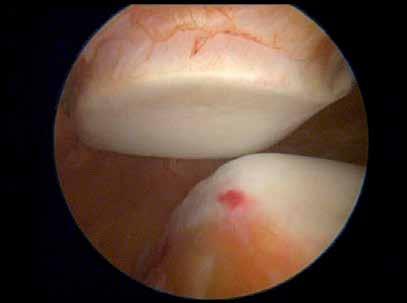

In patellar maltracking, which is usually lateral maltracking, rather than the patella sitting in the groove it tracks over the lateral femoral condyle, on occasions it can be seen to actually overlap the femoral condyle. When the patella tracks in this way it touches the femoral condyle causing pain. So someone with patellar maltracking would have considerable pain in the knee joint as they kneel or in any activity that requires flexion of the knee joint. The pain of the condition makes activities of daily living difficult. The constant wear of the patella on the lateral femoral condyle initially leads to cartilage

damage, followed by erosion and loss of the cartilage finally with the wear of bone on bone to eburnation. Figure below, Siddiqui (2013), patellar maltracking as the knee joint is bent from 0 through to 90 degrees.

Normal patella tracking

Arthroscopic views of maltracking patella as the knee is flexed (Siddiqui 2013).